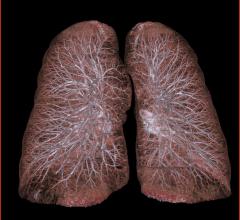

Automatic Deformable Alignment Significantly Reduces Radiologist Time to Match Lung Nodule Locations

August 28, 2013 — Medical software developer Blackford Analysis announced that picture archiving and communications…